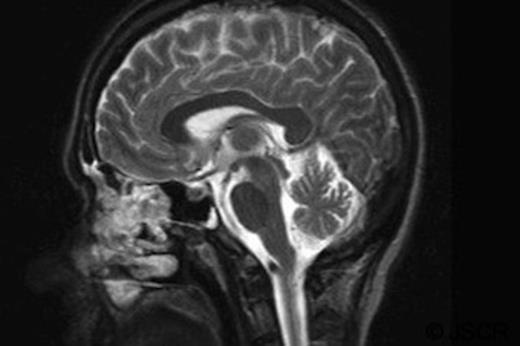

Laboratory finding, (including tumour markers AFP, Ca 19-9, CA125 and CEA) and autoimmune screening tests (ANCA and ANA) were normal. Autoimmune anti-yo antibodies were positive. CT chest/abdomen/pelvis and ultrasound of pelvis were normal. MRI of the brain (Figure 1) and lumbar puncture were normal.

This patient is more in line with the subjects in the majority of literature. She remains unable to ambulate independently and treatment has not thus far led to a long term symptomatic resolution. This case highlights the challenges surrounding the diagnosis of paraneoplastic syndrome in breast cancer patients. Effective treatment is limited and quality of life years markedly affected. Imaging is poor at diagnosing paraneoplastic syndrome and cerebellar changes are variably noticeable on MRI.